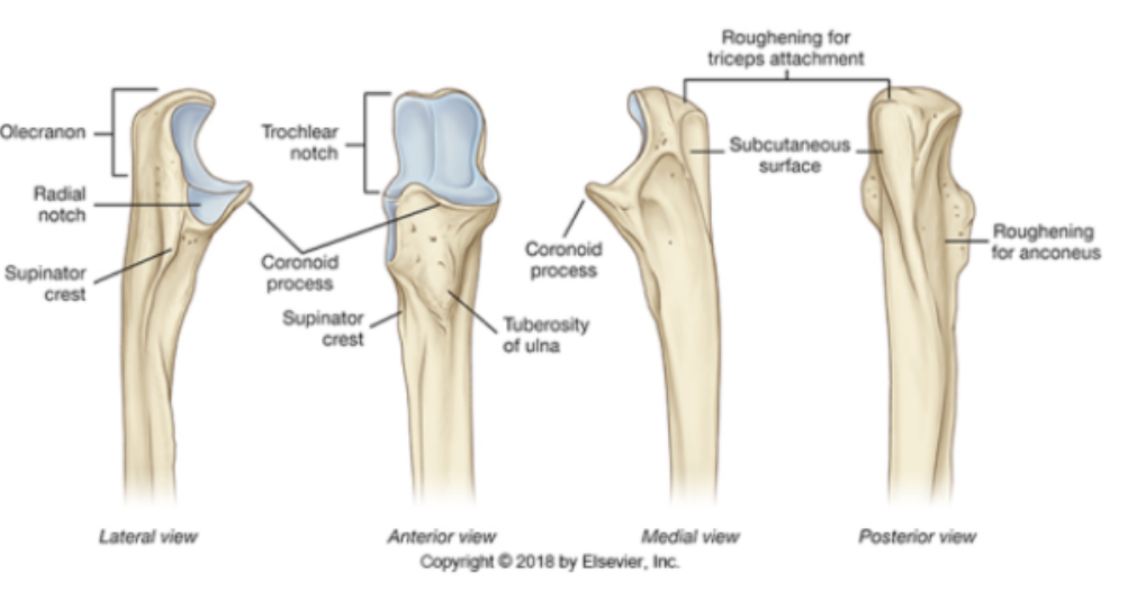

label the parts of the ulna

the suppinator attatches to the suppinator crest

anconeus attatches to roughening for acconeus

Ulna bone

1) Olecranon process

2) Trochlea notch (hosts trochlea of humerus)

3) Radial notch

4) Coronoid Process

5) Ulnar tuberosity

What attaches at the supinator crest of the ulnar?

supinator muscle

What is the roughening for aneconeus?

attachment of the aneconeus muscle

What is the ulnar styloid process?

pointed projection on lateral surface of ulnar head which allows for attachment of different ligaments